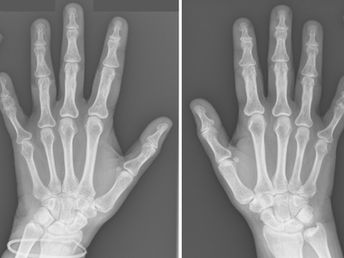

Brachydactyly Type A3

50-year-old female presenting with short 5th finger . What is the diagnosis? • Xray of the Week Figure 1. Frontal bilateral hand X-ray. What is the diagnosis? Figure 2. Frontal bilateral hand X-ray: Severe shortening of the middle phalanx of the fifth digit (red arrows). The phalanx measures less than 50% of the length of the adjacent fourth middle phalanx, satisfying the Hertzog criteria for Brachydactyly Type A3. A mild radial clinodactyly is present, secondary to the wedg